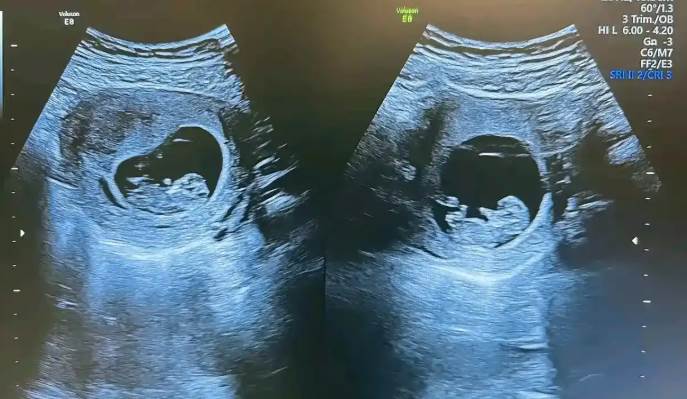

近日,媒體報道一則全球罕見的案例。在2022年,巴西一名未具名女子產下一對雙胞胎,八個月後親子鑑定時,竟發現兩名孩子父親不同,這是全球罕見的「異父異卵超受精」案例,至今全球僅約20例。

負責此案的婦產科醫師稱,異父異卵超受精或因女性一次排卵期釋出多顆卵子,短時間內與不同男性受精,或因短時間內兩次排卵各自受精。孩子雖共享母親基因,但在不同胎盤成長,懷孕過程順利無併發癥。值得一提的是,其中一名男子擔起兩個孩子的父職,將兩人正式登記為其子女並提供照顧支援。